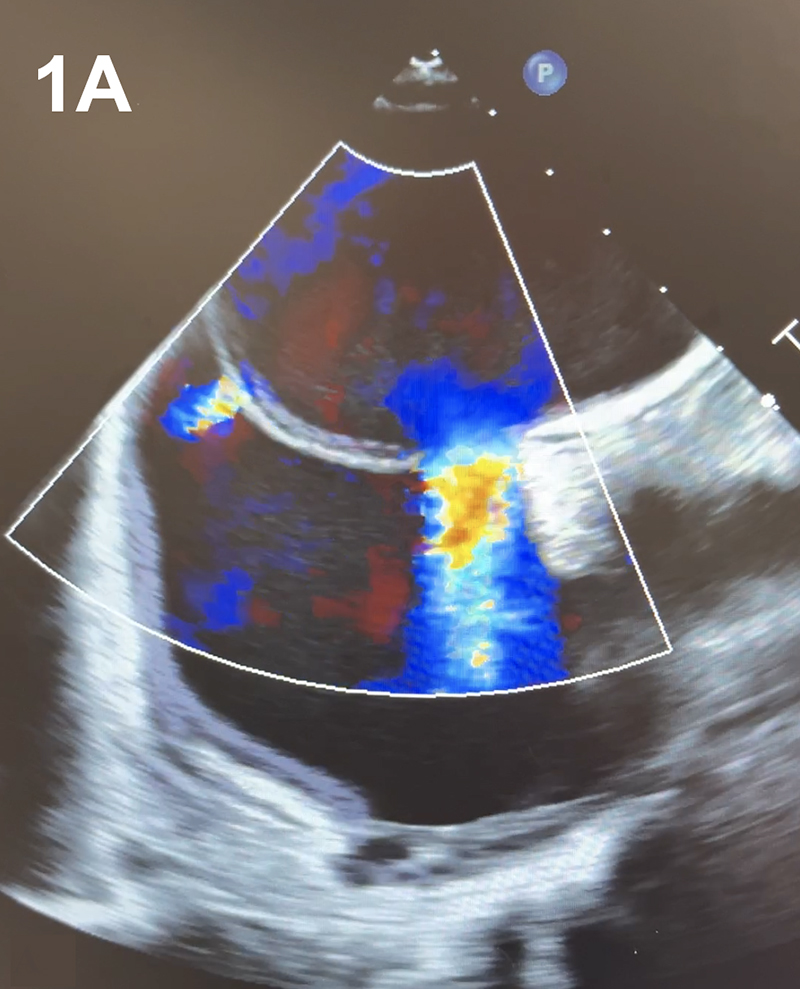

A 41-year-old man with no significant past medical history presented with a cryptogenic cerebrovascular accident (CVA). Brain magnetic resonance imaging (MRI) revealed small, multiple infarcts in the left frontoparietal white matter. Transthoracic echocardiography (TTE) demonstrated right heart enlargement, a large patent foramen ovale (PFO) with an atrial septal aneurysm (ASA) and high-risk features for paradoxical embolism. Planned percutaneous PFO closure was modified intra-procedurally when transesophageal echocardiography (TEE) revealed two distinct ostium secundum ASDs (Figure 1A–B). Right and left atrial pressures measured 10 mmHg and 18 mmHg, respectively. The 21 mm and 8 mm defects were consistent with a large fenestrated ASD with predominant left-to-right shunting. Dual-device closure was pursued to ensure complete occlusion. A 24 mm Amplatzer septal occluder (ASO) was deployed for the larger defect, and a 30 mm cribriform ASO for the smaller defect (Figure 1C–D). TEE confirmed stable device positioning and complete closure with no residual shunting. The patient tolerated the procedure well with no complications.

Figure 1. (A–D) Two-dimensional transesophageal echocardiography (TEE) with color Doppler demonstrates two distinct atrial septal defects with left-to-right shunting (A). TEE confirms successful closure of both defects following implantation of dual Amplatzer septal occluder devices (C). Fluoroscopic imaging during the procedure shows the positioning of both occluder devices (D).